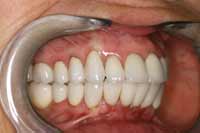

The patient returned 1 month later for computerized occlusal analysis. The analysis objectively confirmed that the occlusion was balanced and right and left cuspid disclusion as well as protrusion were immediate and measurable to less than 0.2 seconds. The patient was reevaluated at 6 months, 1 year, and 3 years posttreatment. Her symptoms have not returned. Follow-up examinations using biometric instrumentation objectively show normal healthy muscle function, normal jaw function, normal swallowing, and a normal airway. The patient is ecstatic with her final result (Figure 17 through Figure 19).

Figure 17 Completed case, right-side view.

Figure 18 Completed case, left-side view.

Figure 19 Completed case. The patient was pleased with her final smile